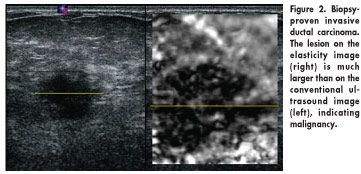

In the study, lesions were graded as malignant or benign based on the difference in their size on conventional B-mode ultrasound and elasticity imaging. If a lesion was smaller on elasticity imaging than on B-mode ultrasound, it was classified as benign (Figure 1); if larger, it was considered malignant (Figure 2).